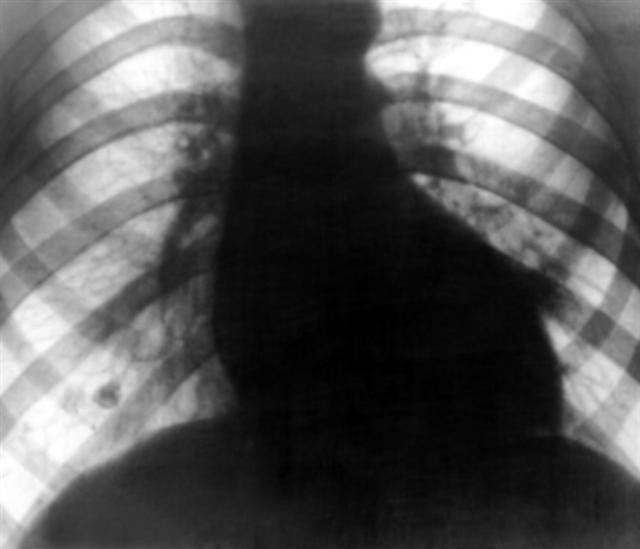

Рис. 16. Рентгенограмма грудной клетки больного с аортальным стенозом: поперечник сердечной тени увеличен влево, талия сердца резко выражена, дуга левого желудочка удлинена и закруглена («аортальная» конфигурация).